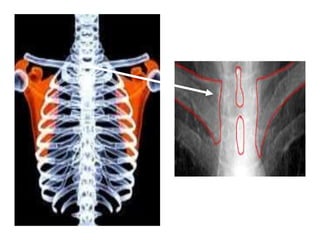

This document provides an overview of interpreting chest x-rays and identifies several key factors. It discusses the importance of inspiration, penetration, and rotation in obtaining a technically quality radiograph. It also outlines different views of chest x-rays including PA, AP, and lateral views. Finally, it identifies several anatomical structures that should be evaluated when interpreting a chest x-ray such as the lungs, heart, diaphragm, bones, and soft tissues.